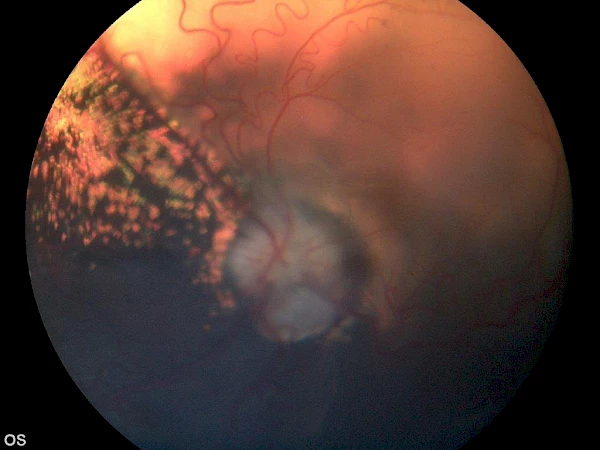

Beispiel einer erfolgreichen Netzhautoperation inkl. Endolaser, von Chris Dixon Beispiel einer erfolgreichen Netzhautoperation inkl. Endolaser, von Chris Dixon

angeborene Netzhautablösung, ein geeigneter Kandidat für eine erfolgreiche Netzhautoperation angeborene Netzhautablösung, ein geeigneter Kandidat für eine erfolgreiche Netzhautoperation

vor Operation vor Operation